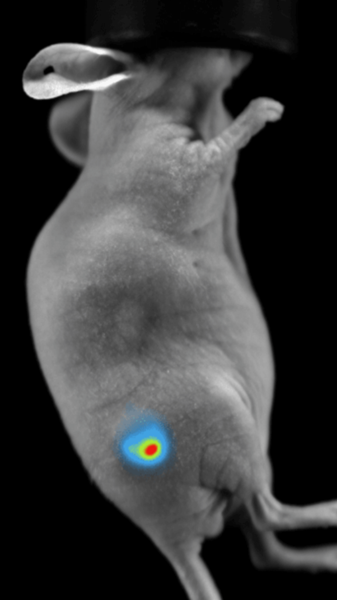

Subcutaneous tumor expressing mCherry. Image Credit: Scintica Instrumentation Inc

Bioluminescence imaging

Luciferase-expressing or secreting molecules in the target tissue can be found via bioluminescence imaging.

Subcutaneous tumor expressing firefly luciferase. Image Credit: Scintica Instrumentation Inc